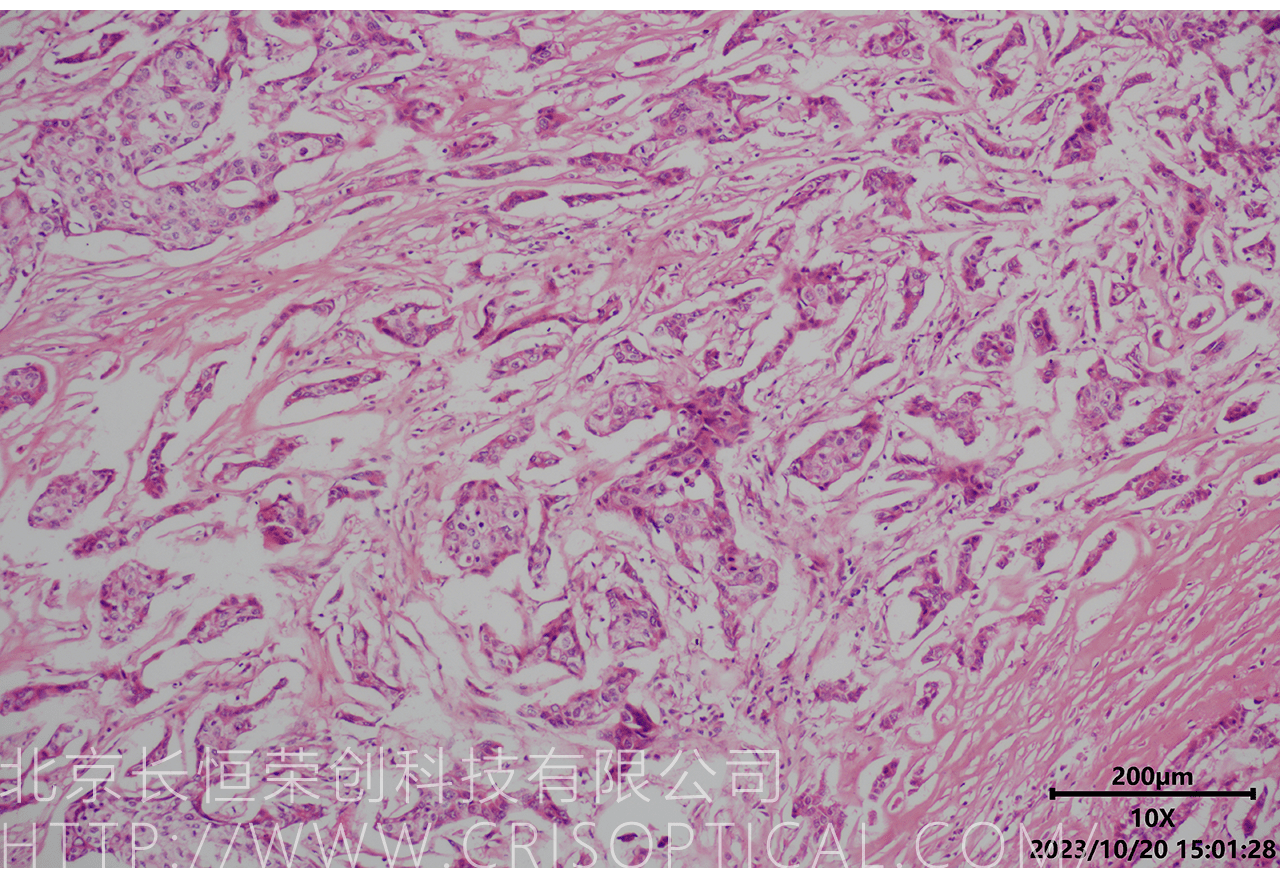

腫瘤診斷:對(duì)癌癥和其他腫瘤的病理切片觀察是確定腫瘤類型、分級(jí)和分期的關(guān)鍵步驟。醫(yī)生通過(guò)觀察組織樣本中的細(xì)胞形態(tài)、核形狀、分裂活性和其他特征,可以識(shí)別腫瘤的類型,幫助決定治療方法。